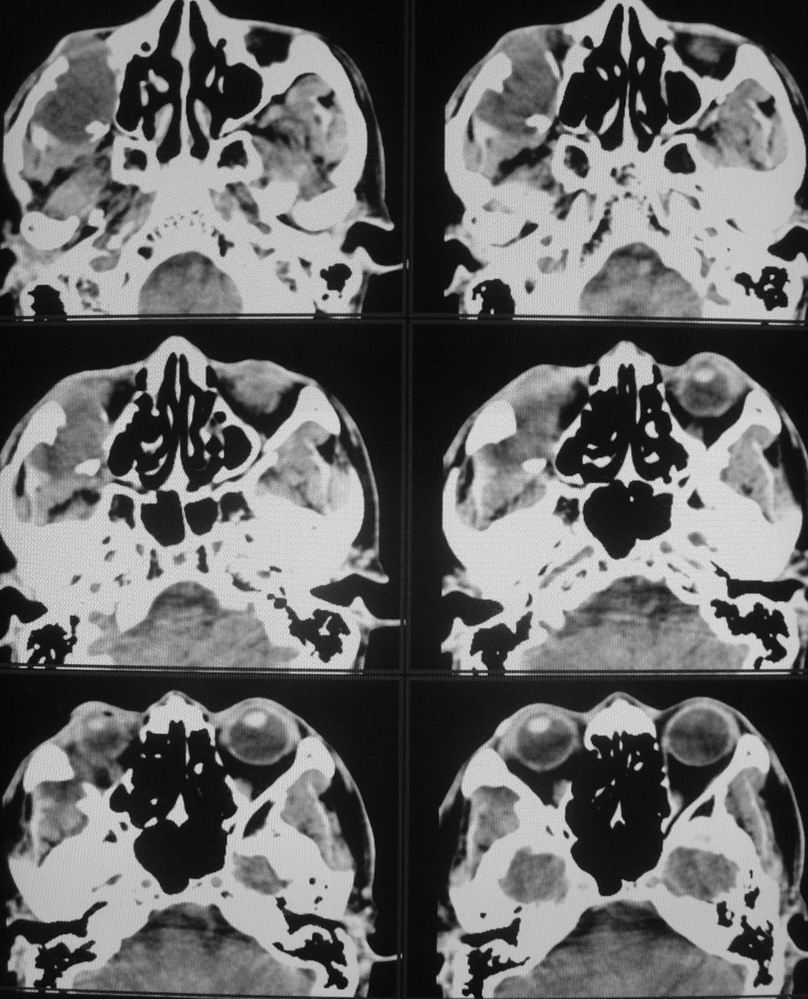

以下是引用zsl6918在2008-5-6 14:41:00的发言:[br]右侧颞下窝内囊性占位(增强未见强化),同侧上颌窦受压变形移位,提示慢性过程。右侧上颌骨局限性吸收破坏,提示良性病变。

以下是引用长城干红在2008-5-6 15:05:00的发言:[br]考虑:右侧颞下窝神经源性良性肿瘤。

以下是引用xuhuihong在2008-5-6 14:57:00的发言:[br]右侧颞下窝内囊性占位(增强未见强化),同侧上颌窦受压变形移位骨质吸收变薄,提示慢性过程。右侧上颌骨局限性吸收破坏,提示良性病变。考虑神经源性肿瘤可能,期待结果。